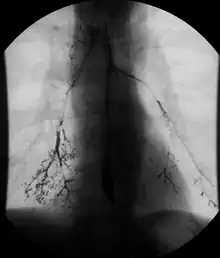

- Enteroclysis, also called small bowel enema, is a barium X-ray examination used to display individual loops of the small intestine by intubating the jejunum and administering barium sulfate followed by methylcellulose or air.[5]

Enteroclysis

Enteroclysis is also known as small bowel enema.[21] It has been largely replaced by magnetic resonance enterography/enteroclysis[13] and computed tomography enterography/enteroclysis.[22]

In addition to fasting for 8 hours prior to examination, a laxative may also be necessary for bowel preparation and cleansing.[12] The main aim of this study is to distend the proximal bowel through infusion of large amount of barium suspension. Otherwise, the distension of distal small bowel is generally similar with small bowel follow-through. Therefore, there is a need to pass a tube through the nose into the jejunum (nasojejunal tube) to administer large amount of contrast. This can be unpleasant to the subject, requires more staff, longer procedural time, and higher radiation dose when compared to small bowel follow-through. The indications for enteroclysis are generally similar to small bowel follow-through. Barium suspensions such as diluted E-Z Paque 70% and Baritop 100% can be used. After that, 600 ml of 0.5% methylcellulose is administered after 500 ml of 70% barium suspension is given. Bilbao-Dotter tube and Silk tube can be used to administer barium suspension. The subject should be fasted overnight, any antispasmodic drugs should be stopped one day before the examination, and Tetracaine lozenges can be used 30 minutes before the procedure to numb the throat for nasojejunal tube insertion.[13]

The filling of the small intestines can be viewed continuously using fluoroscopy, or viewed as standard radiographs taken at frequent intervals. The technique is a double-contrast procedure that allows detailed imaging of the entire small intestine. However, the procedure may take 6 hours or longer to complete and is quite uncomfortable to undergo.[23]

- Enteroclysis has shown to be very accurate in diagnosing small bowel diseases, with a sensitivity of 93.1% and specificity of 96.9%. It permits detection of lesion which may not be seen with other imaging techniques.[7] There is no significant difference in terms of detection of clinically significant findings, sensitivity or specificity between enteroclysis and CT enterography.[1] Enteroclysis compares favorably with wireless capsule endoscopy and double-balloon endoscopy in the diagnosis of mucosal abnormalities of the small bowel.[24]